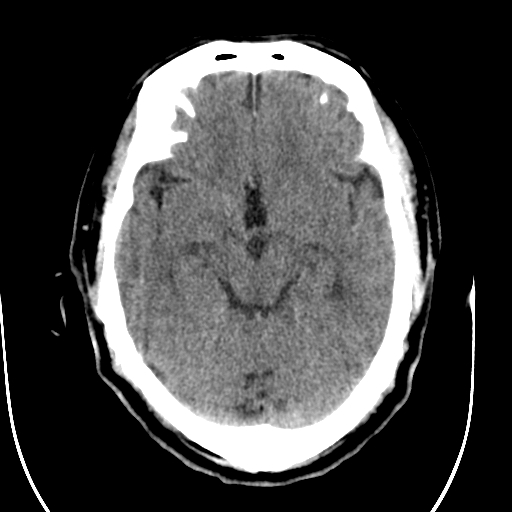

标题: CT28335:男,58岁,请各位看看是不是有脑积水,蝶窦内高密 [打印本页]

标题: CT28335:男,58岁,请各位看看是不是有脑积水,蝶窦内高密

轻度积水,蝶窦正常。

1)脑积水。2)副鼻窦炎。